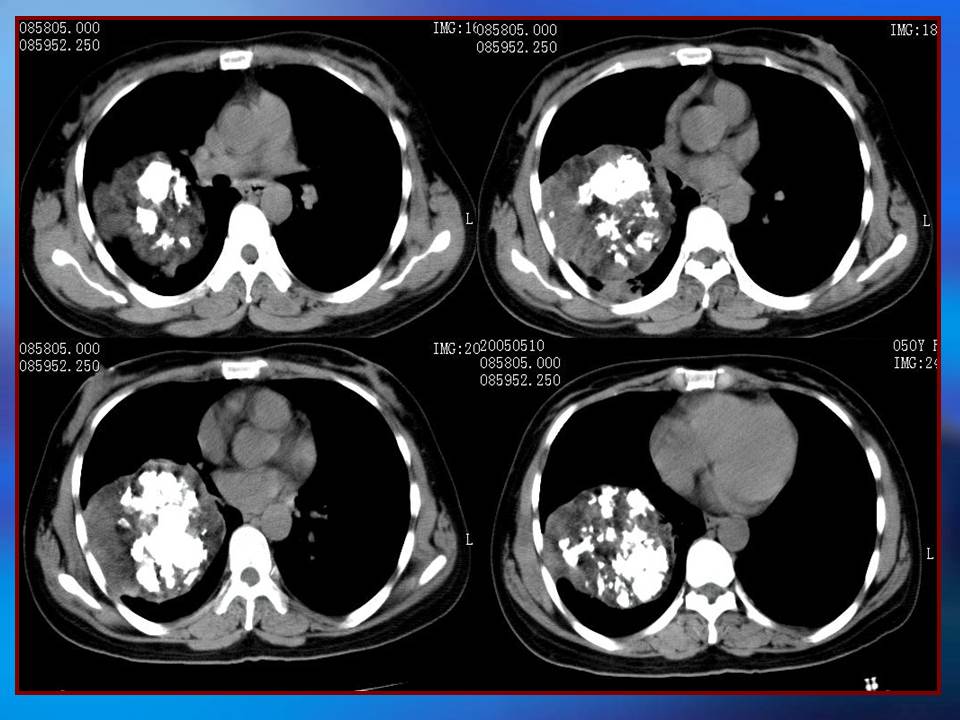

肺良性肿瘤